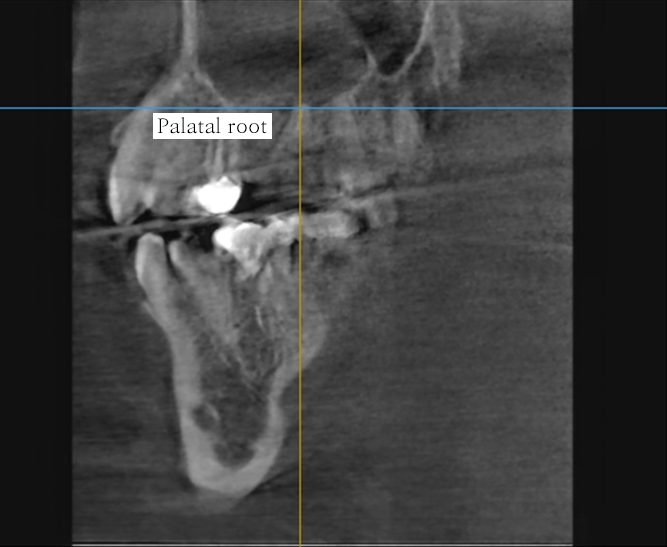

CT 영상(초진)과 standard x-ray 사진(팔라탈 루트 발치 후)

이번 주에 있었던 임상 케이스는 발치 후 생긴 상악동 누공이다. 이미 치관은 썩어 날아갔고 엔도도 되어있었다. 드러난 치근 중간에 GP로 추정되는 연핑크 실오라기가 몇가닥 꼽혀있는 루트레스트 발치케이스. 파노라마상에서 치근이 상악동 내부로 돌출되어 보이기도 하고 반대편엔 cystic lesion도 있어서 술전에 대표원장님께서 미리 CT도 찍어보았는데, 역시나 상악동 내부로 루트가 솟아올라와 있었다. 발치 중에 상악동으로 치근이 전위될 수 있음을 고지하고, 상악동에 구멍이 날 수 있다는 이야기도 반복적으로 설명한 뒤에 동의를 받고 발치를 시작했다.